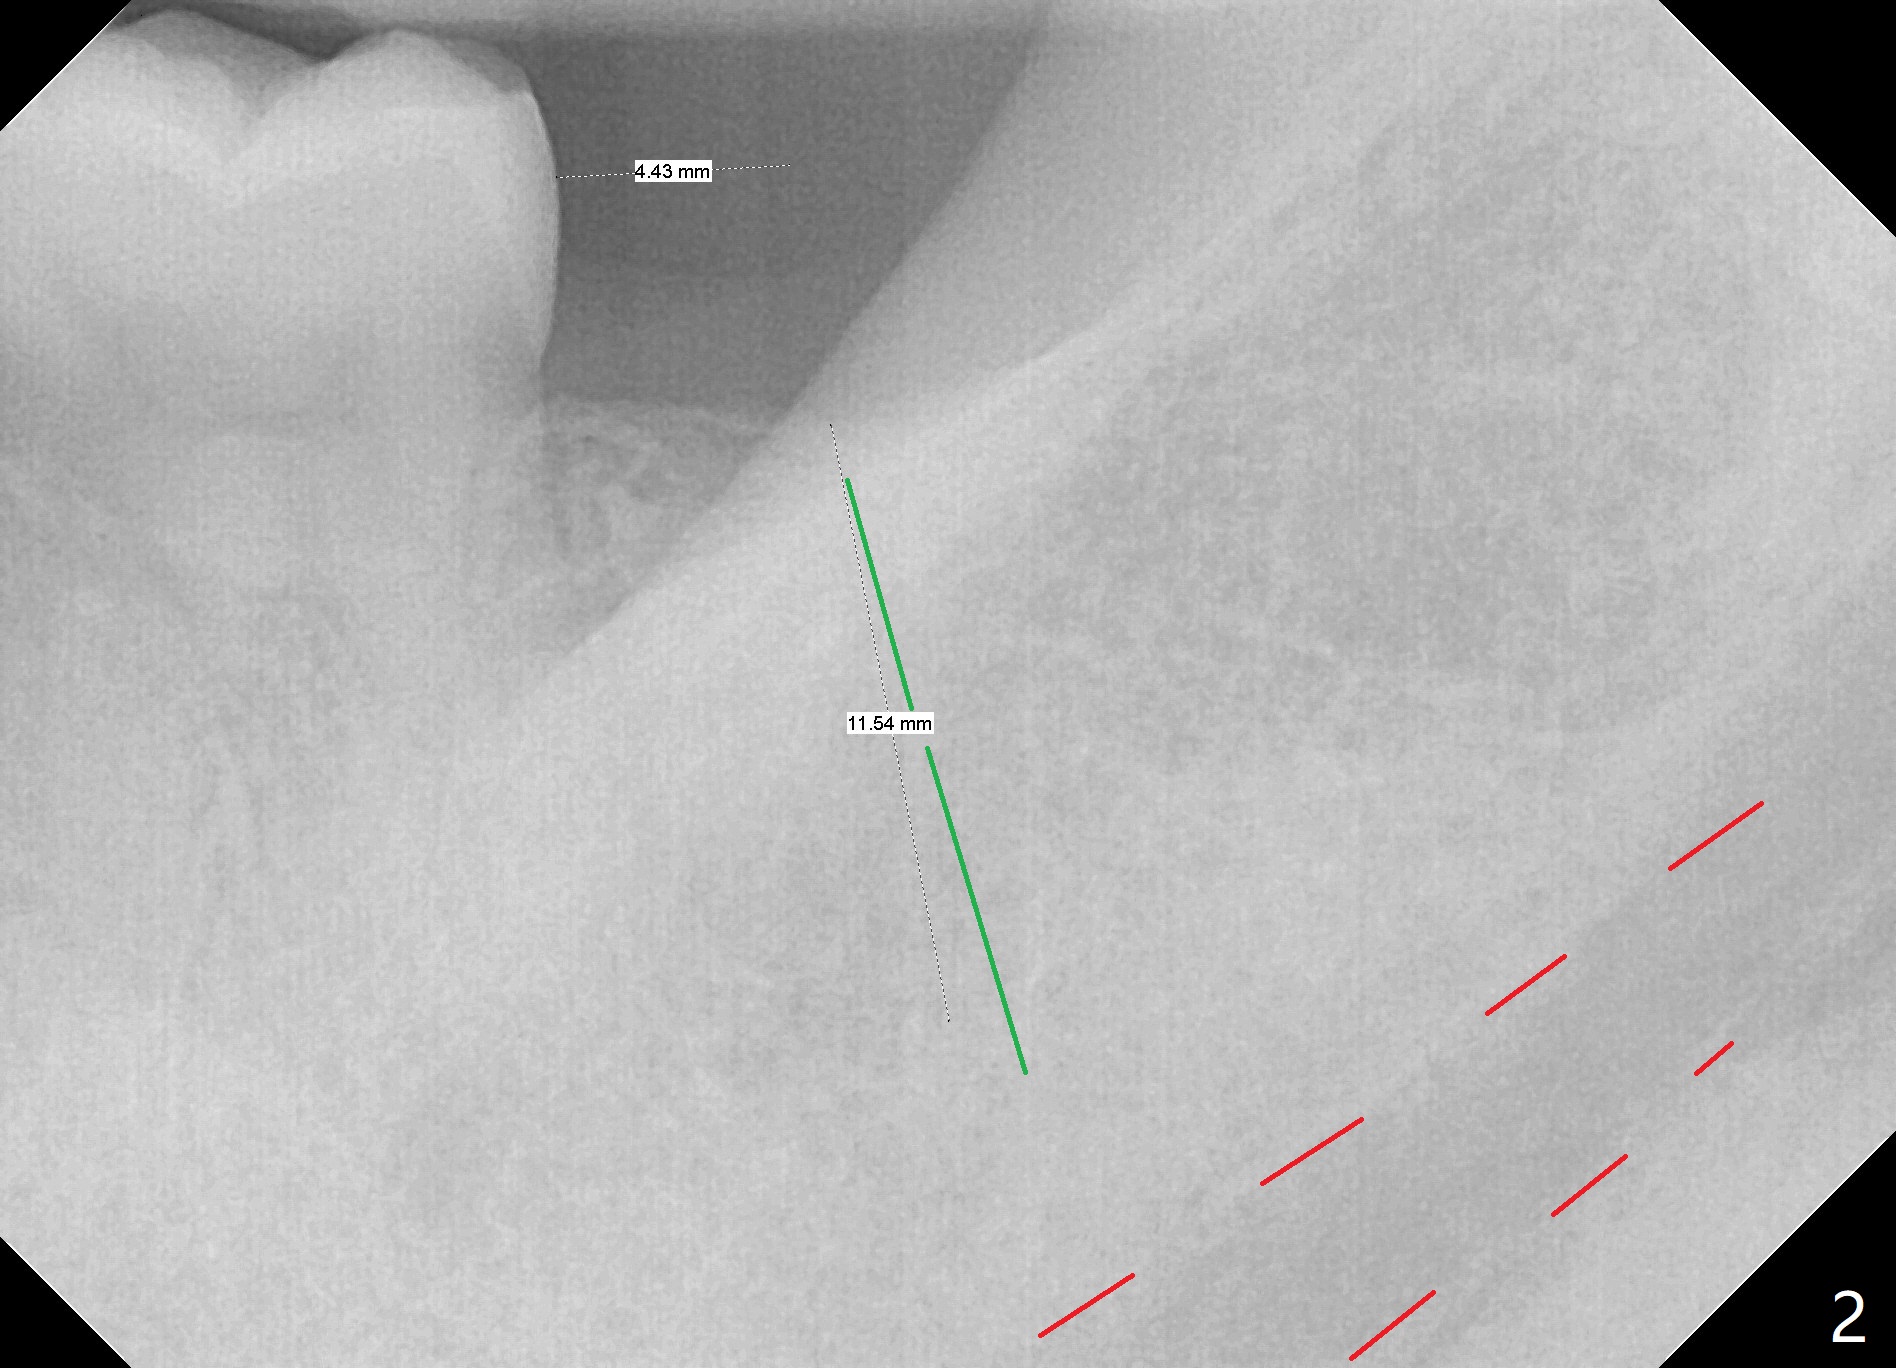

A 42-year-old man has lost #18 (due to 3rd molar impaction) for ~ 5 years (Fig.1). Because of the indistinct Inferior Alveolar Canal (Fig.3 ? vs. Fig.2 red dashed line), CBCT is taken for guided surgery (Fig.4: 5x11.5 mm).